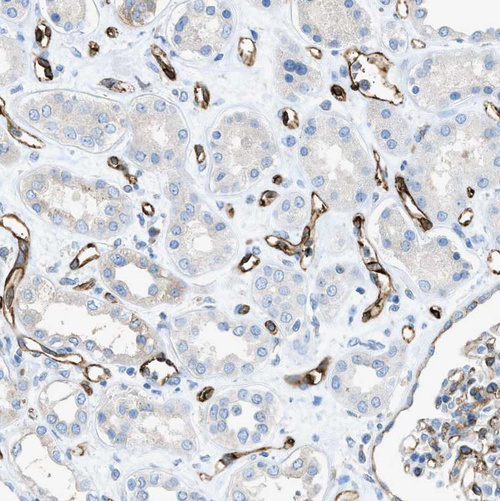

Immunohistochemical staining of human bone marrow shows strong cytoplasmic positivity in megakaryocytes.